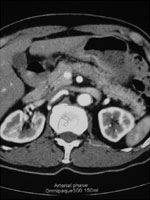

Pre-operative CAT scan

AAA size 5.2 cm

AAA stent graft(Cook Zenith) + Lt iliac stenting + Lt internal iliac embolization

平成18年1月CTにて増大傾向を認め当院紹介受診。